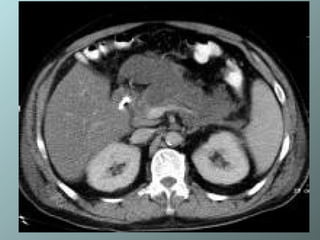

Pancreatitis focal que compromete la cabeza del páncreas, que se ve agrandada con inflamación peripancreática mal definida y colecciones de fluidos

Pancreatitis focal quecompromete la cabeza del páncreas, que se ve agrandada con inflamación peripancreática mal definida y colecciones de fluidos